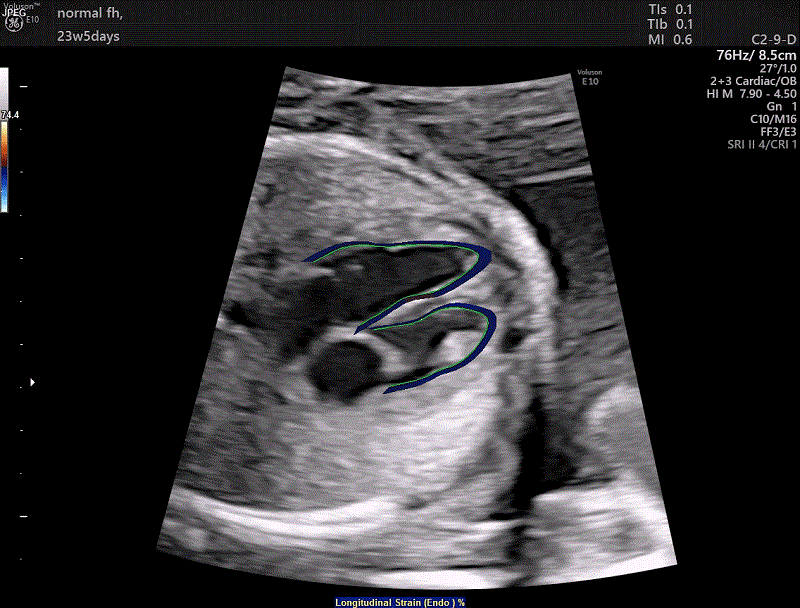

یک تصویر دو بعدی (مطالعه 2 بعدی و 3 بعدی) از قلب جنین می سازد که همانطور که در ویدیوی بالا سمت چپ مشاهده می شود، روی صفحه نمایش داده می شود و قلب طبیعی جنین را با 4 حفره نشان می دهد.

اهداف اکوکاردیوگرافی جنین

هدف اصلی اکوکاردیوگرام جنین، تشخیص زودهنگام بیماری قلبی مادرزادی و آریتمی جنین است. در اولین ویدیوی فوقانی، کانال av جنین مشاهده می شود (یک نقص بزرگ سپتوم یا ASD بالای دریچه هایی که باز و بسته می شوند و یک نقص سپتوم کوچکتر در زیر آنها مشاهده می شود که VSD است.ASD و VSD معمولی کانال AV هستند. ). ویدئوی دوم بالا قلب جنینی را با تنها یک بطن نشان می دهد، این یک مورد بطن منفرد است. همچنین هنگامی که مشکوک یا شواهدی مبنی بر تغییرات همودینامیک (عملکرد کلی سیستم گردش خون) جنین ناشی از سایر مشکلات غیر خاص قلبی، مانند تاخیر در رشد داخل رحمی، هیدروپس جنینی با منشأ ایمنی یا انتقال خون دوقلو وجود دارد، کمک می کند. در این موارد، اکوکاردیوگرافی جنین می تواند تشخیص نارسایی قلبی احتمالی جنین را به دلیل این مشکلات اصلاح کند. بنابراین، هدف نهایی مطالعه قلب جنین، ارائه تمام اطلاعات موجود در آن زمان در مورد بیماری قلبی احتمالی کودک آینده به والدین آینده و متخصص زنان و زایمان است. ما به عنوان متخصصان با آگاهی از رنجی که والدین آینده اخبار بیماری قلبی جنین را دریافت می‌کنند، تلاش می‌کنیم تا با پرهیز از سوگیری در یک جهت یا آن، جزئیات ممکن را در مورد ماهیت، درمان و پیش‌آگهی بیماری قلبی در اختیار آنها قرار دهیم. امروزه تمام بیماری های مادرزادی قلبی دارای امکانات واقعی برای درمان هستند و در بیشتر موارد، نوزاد آینده کیفیت زندگی خوب یا قابل قبولی خواهد داشت.